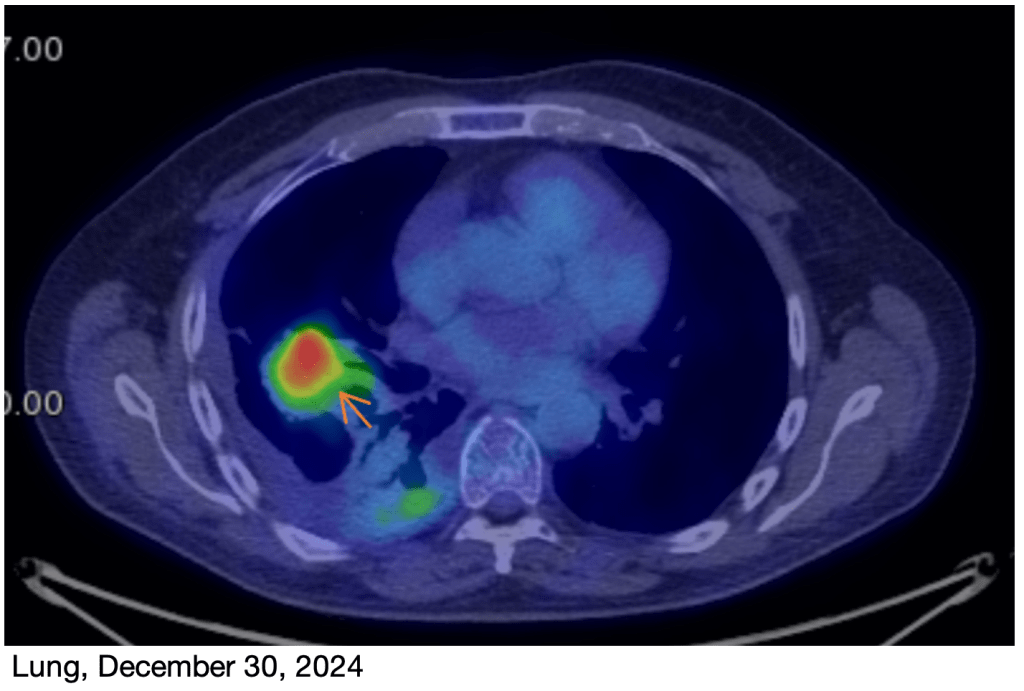

March PET Scan: I just had a new PET scan on Monday, and the results are great! The tumor on my rib is basically gone, and the primary tumor in my lung is now very small, just a faint reminder of what it was! This is obviously great news! I’ll have another scan in June.